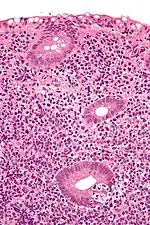

Micrograph showing a lymphoepithelial lesion (lower right of image) in a primary gastrointestinal tract lymphoma. H&E stain.

In pathology, lymphoepithelial lesion refers to a discrete abnormality that consists of lymphoid cells and epithelium, which may or may not be benign.

It may refer to a benign lymphoepithelial lesion of the parotid gland or benign lymphoepithelial lesion of the lacrimal gland, or may refer to the infiltration of malignant lymphoid cells into epithelium, in the context of primary gastrointestinal lymphoma.[1]

In the context of GI tract lymphoma, it is most often associated with MALT lymphomas.[1]